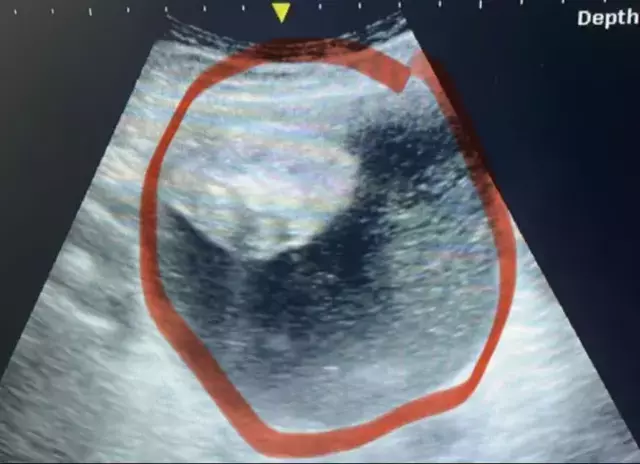

Yapılan testler sonucunda hamile olmadığı ortaya çıkan Gerrits, ultrason ve ileri tetkiklere alındı. Başta ne olduğu anlaşılamayan bu şişliğin mesaneye baskı yapan sıvı dolu bir kitle olduğu tespit edildi. Ancak kesin tanı ancak günler sonra yapılan jinekolojik muayene ile konulabildi: Yumurtalık tümörü...

Hastalığın ilerlemesi oldukça hızlıydı. Cuma günü yapılan ölçümde 12 santimetre olan kitle, Pazartesi günü 17 santimetreye ulaştı. Bu hızlı büyüme nedeniyle Gerrits acil ameliyata alındı. Tümör ameliyat sırasında patladı ancak bu durum, hastalığın yayılmadan kontrol altına alınmasında önemli bir şans olarak değerlendirildi.